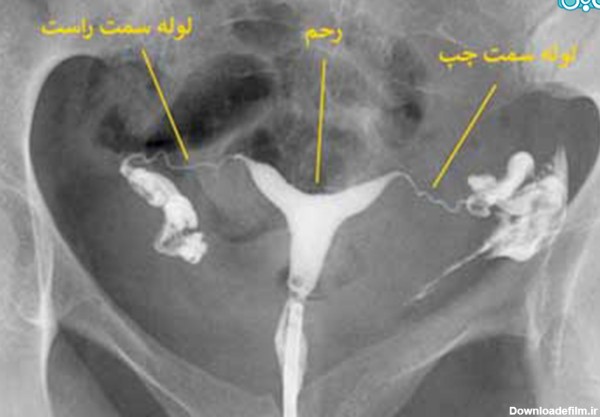

عکس رنگی رحم یا هیستروسالپنگوگرافی روشی است که به منظور بررسی داخل رحم و لوله های رحمی انجام می گیرد و انجام آن در ارزیابی ناباروری بسیار مهم است.

عکس رنگی رحم یا هیستروسالپینگوگرافی به معنای استفاده از اشعه ایکس برای مشاهده رحم و لولههای فالوپ است.